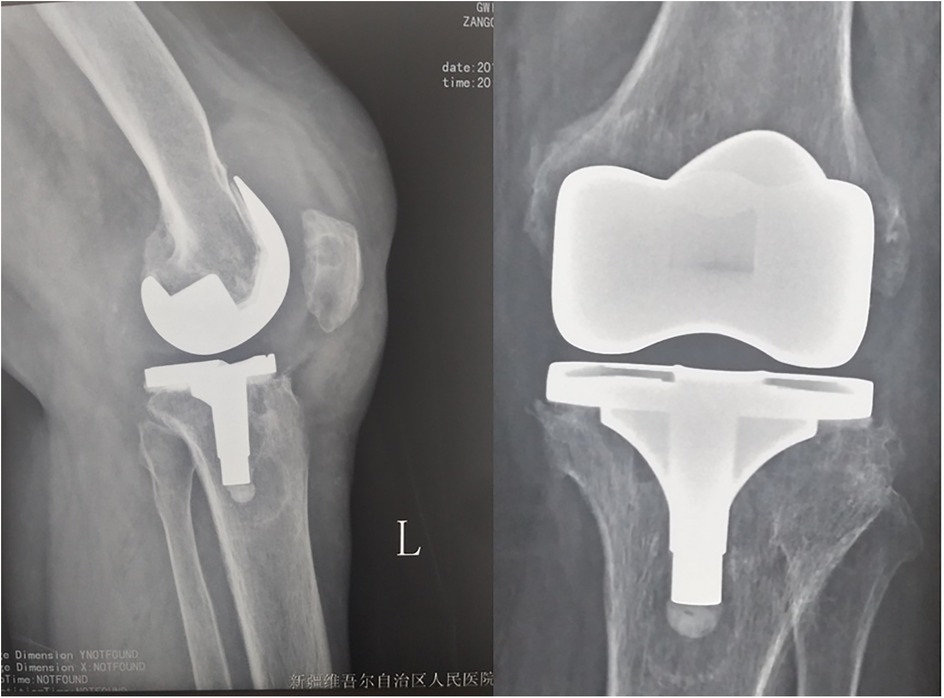

Surgical procedures were performed under general anesthesia. For knee revisions, a standard medial parapatellar arthrotomy was used with a tourniquet. For hip revisions, a posterolateral approach was employed. During the operation, purulent or necrotic tissue around the prosthesis was observed. Purulent fluid was turbid and pale yellow, with synovial hyperplasia edema and synovial partial necrosis (Figure 3). We performed debridement first; pulse pulse lavage helped to eliminate Brucella bacillus. After this step, the gloves were changed, and a new operation instrument was used for revision. After debridement and installing the prosthesis, pulse lavage was performed after the bone cement was dry, and doxycycline powder (100 mg) was used directly around the prosthesis. No drainage tube was placed. The most conclusive means of establishing a diagnosis of brucellosis is positive cultures from normally sterile body fluids or tissues. During the operation, pus was cultured, and the tissues were removed and sent for routine pathological examination. Synovial fluid and tissue samples were collected for Brucella culture on specific media and PCR analysis using species-specific primers. Post-operation x-ray exam shows good position of prosthesis (Figure 4), and patients feel good also have good function (Figure 5).

Figure 4. Post-operation x-ray shows no prothesis loosening happened, implants placed good position.